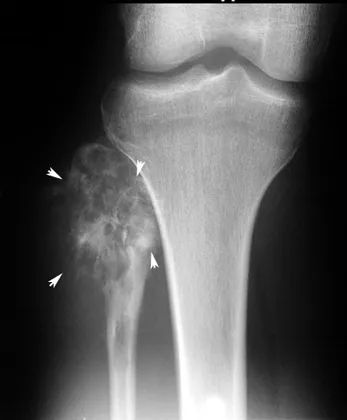

在X光片中,骨肉瘤有阳光四射一样的形态(sunburst)。梅奥医学中心的肿瘤血液学家 Carola Arndt 介绍,骨肉瘤是最恶性的骨癌之一。

骨肉瘤有阳光四射一样的形态

图片来源:芝加哥大学医学院